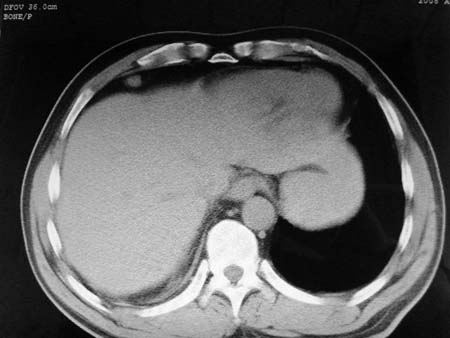

以下是引用qian在2008-4-27 17:02:00的发言:[br]考虑右下肺肺段隔离症伴有感染,建议做增强看看。

以下是引用zsl6918在2008-4-27 17:13:00的发言:[br]考虑右肺下叶炎性病变可能性大,建议抗炎治疗后复查,现有资料不能完全除外肺癌可能。